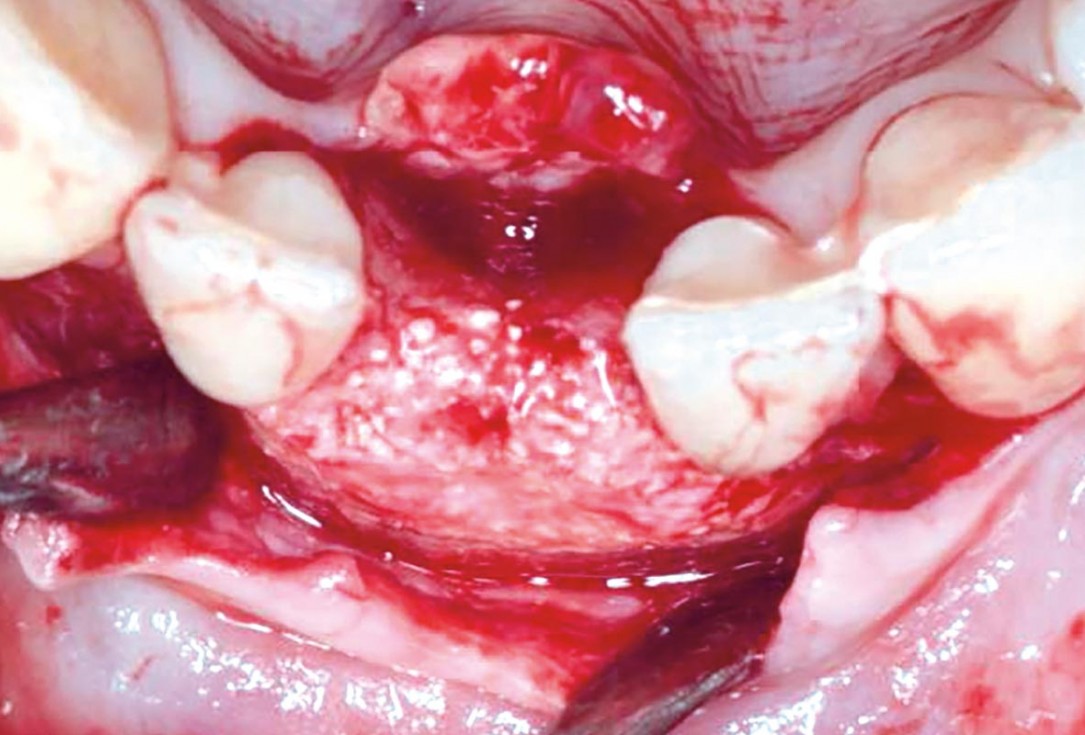

Regenerative corticotomy to compensate lower incisor malocclusion with cerabone® and mucoderm®

Initial view of the clinical case: Class III malocclusion

Treatment plan: Regenerative corticotomy (PAOO)